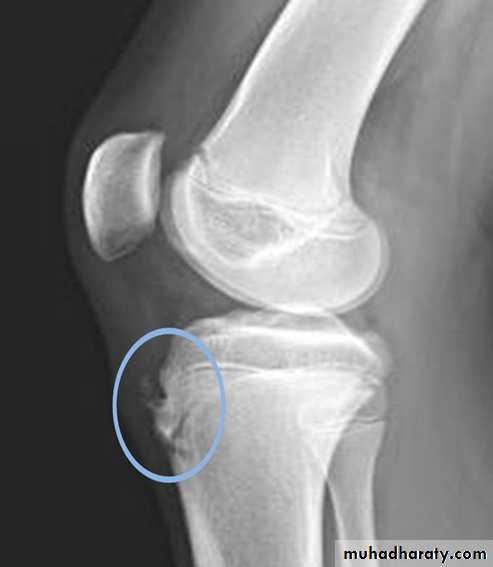

Osteochondritis of

lumbar vertebral bodies (advanced case).Osteochondritis dissecans

affects the large articular surface , commomnly medial femural condylee ,talus and trochlea .Ends by separation of the affected part in to the joint space resulting in intra-articular loose body .

Osteochondritis dissecans of the medial femoral condyle Osteochondritis dissecans of the medial part of the articular surface